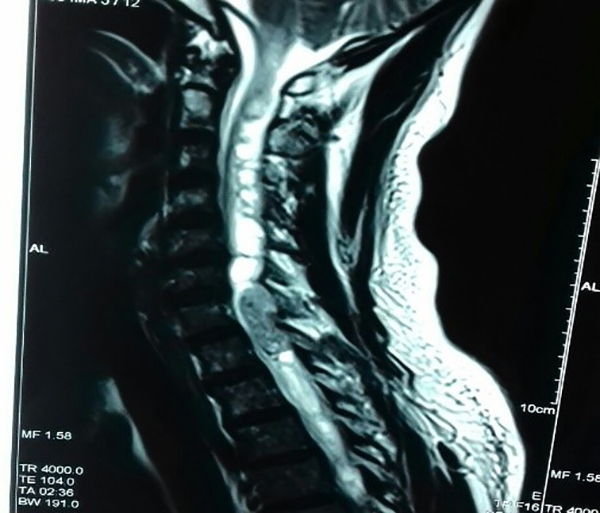

Se trata de un paciente masculino de 44 años de edad, sin antecedentes de importancia para la patología de base, con déficit motor de 2 años de evolución, que inicia a nivel de miembros inferiores y posteriormente afecta también a los superiores hasta provocar dificultad para la marcha. Acude a consulta especializada en silla de ruedas y asistido por familiar con esta historia clínica; se encontró cuadriparesia con paraparesia densa, de predomino derecho, con hiperreflexia generalizada y signo de Babinsky generalizado. Se encontró nivel sensitivo a nivel T5. Se inicia protocolo de estudios de forma inmediata, encontrándose en la RM de médula cérvico-dorsal lesión intraxial a nivel de C7-T1, compatible con probable ependimoma cervical [figura 1]. Se clasifica preoperatoriamente con una Escala de McCormick Modificada, grado 4.

Fig. 1:

RM en secuencia ponderada en T2, donde se observa lesión intrarraquídea ocupante de espacio en la porción cervical baja C7- T1, con siringomielia acompañante, supra e infralesional.